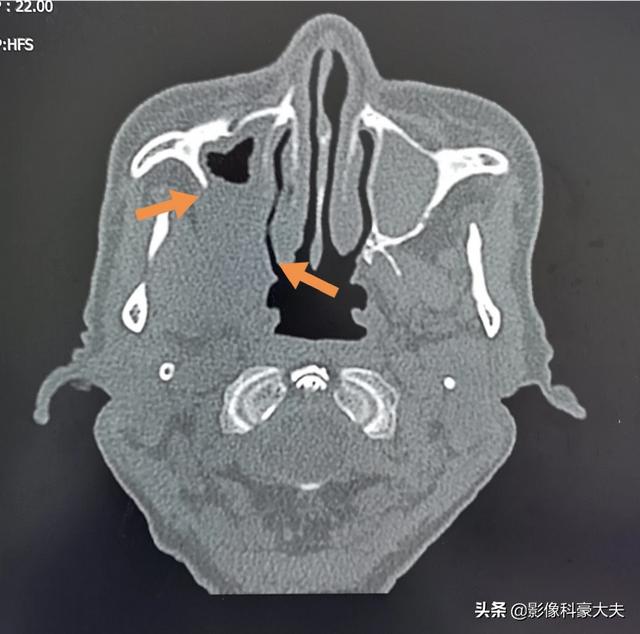

この老人は、右側の歯痛と頬の膀胱の痛みで、2ヶ月以上、歯の根の炎症がある老人のように薬を服用してきたが、現在では上顎洞癌における骨破壊上へ